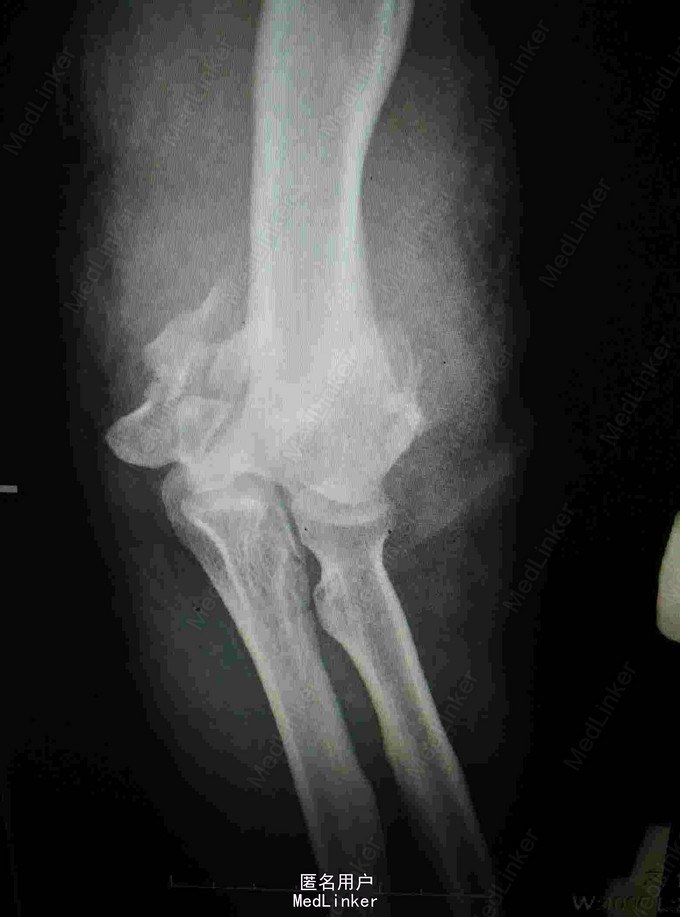

外伤致左肘关节疼痛流血,活动受限4小时 患者青年女性,因不慎摔倒致左肘疼痛流血,当即出现活动受限,肘关节可见骨外露,于当地医院行X线片提示肱骨髁间粉碎性骨折,清创包扎后入我院进一步治疗。

查体:肘关节可见骨外露,活动受限,肘后三角消失,左腕关节左拇指背伸受限,左拇指小指无法对指,五指并指困难,左手皮肤感觉减弱,以拇指小指明显 辅查:肘关节正侧位片提示肱骨髁间粉碎性骨折

诊断:左肱骨髁间粉碎性骨折 左肘关节脱位 左迟神经 桡神经 正中神经损伤 治疗:左肘关节开放伤清创术+外固定架固定术